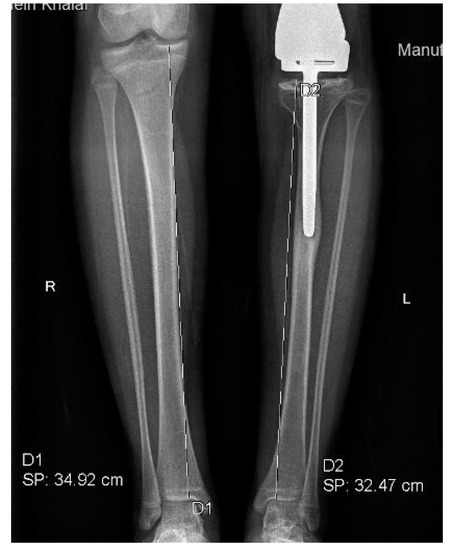

Tibial length discrepancy was discovered in 13 patients with a mean of 12 mm and a median of 10 mm (3–30 mm) (Figure 3). Only three patients had a TLD of 20 mm or greater, three had a TLD of more than 10 mm and less than 20 mm, and the remaining patients showed values of <10 mm. Twelve out of the 13 patients with LLD had concurrent TLD, contributing to 13–100% (59%) of the difference in length. In three patients, LLD was caused entirely by TLD. A histogram of the magnitude of growth disturbance indices in 14 patients is depicted in Figure 4.

Figure 3.

A histogram of the 14 patients who showed radiological evidence of leg length discrepancy.

Figure 4.

Tibial length discrepancy of 24.5 mm in one of our patients.